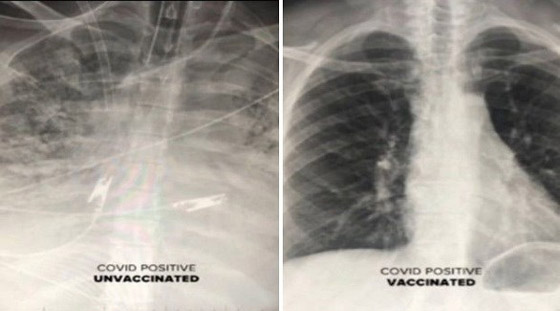

تُظهر عمليات المسح التأثير الصادم لفيروس كورونا على الأعضاء الداخلية للمرضى، حيث قال الأطباء إن الأشخاص غير المطعمين هم من "يصابون بالمرض حقًا". وقال الدكتور سام دوراني من مركز دير فالي الطبي "الأشخاص الوحيدون الذين يمرضون حقًا هم الأشخاص غير المحصنين. وفي كثير من الأحيان يحتاجون إلى التهوية والأكسجين".

وأوضح الدكتور دوراني أن المرضى الذين تم تطعيمهم والذين أصيبوا بفيروس كورونا لديهم المزيد من الهواء المتدفق إلى رئتيهم، مع تلوين الجزء الأكبر من الرئتين باللون الأسود في الفحص، وهذا يعني أن هناك ضررًا ضئيلًا جدًا أو لا يوجد ضرر على الرئتين. وتظهر صورة الفحص من شخص غير محصن أن الرئتين محتقنتان للغاية، مما يحد من تدفق الأكسجين في جميع أنحاء الجسم.